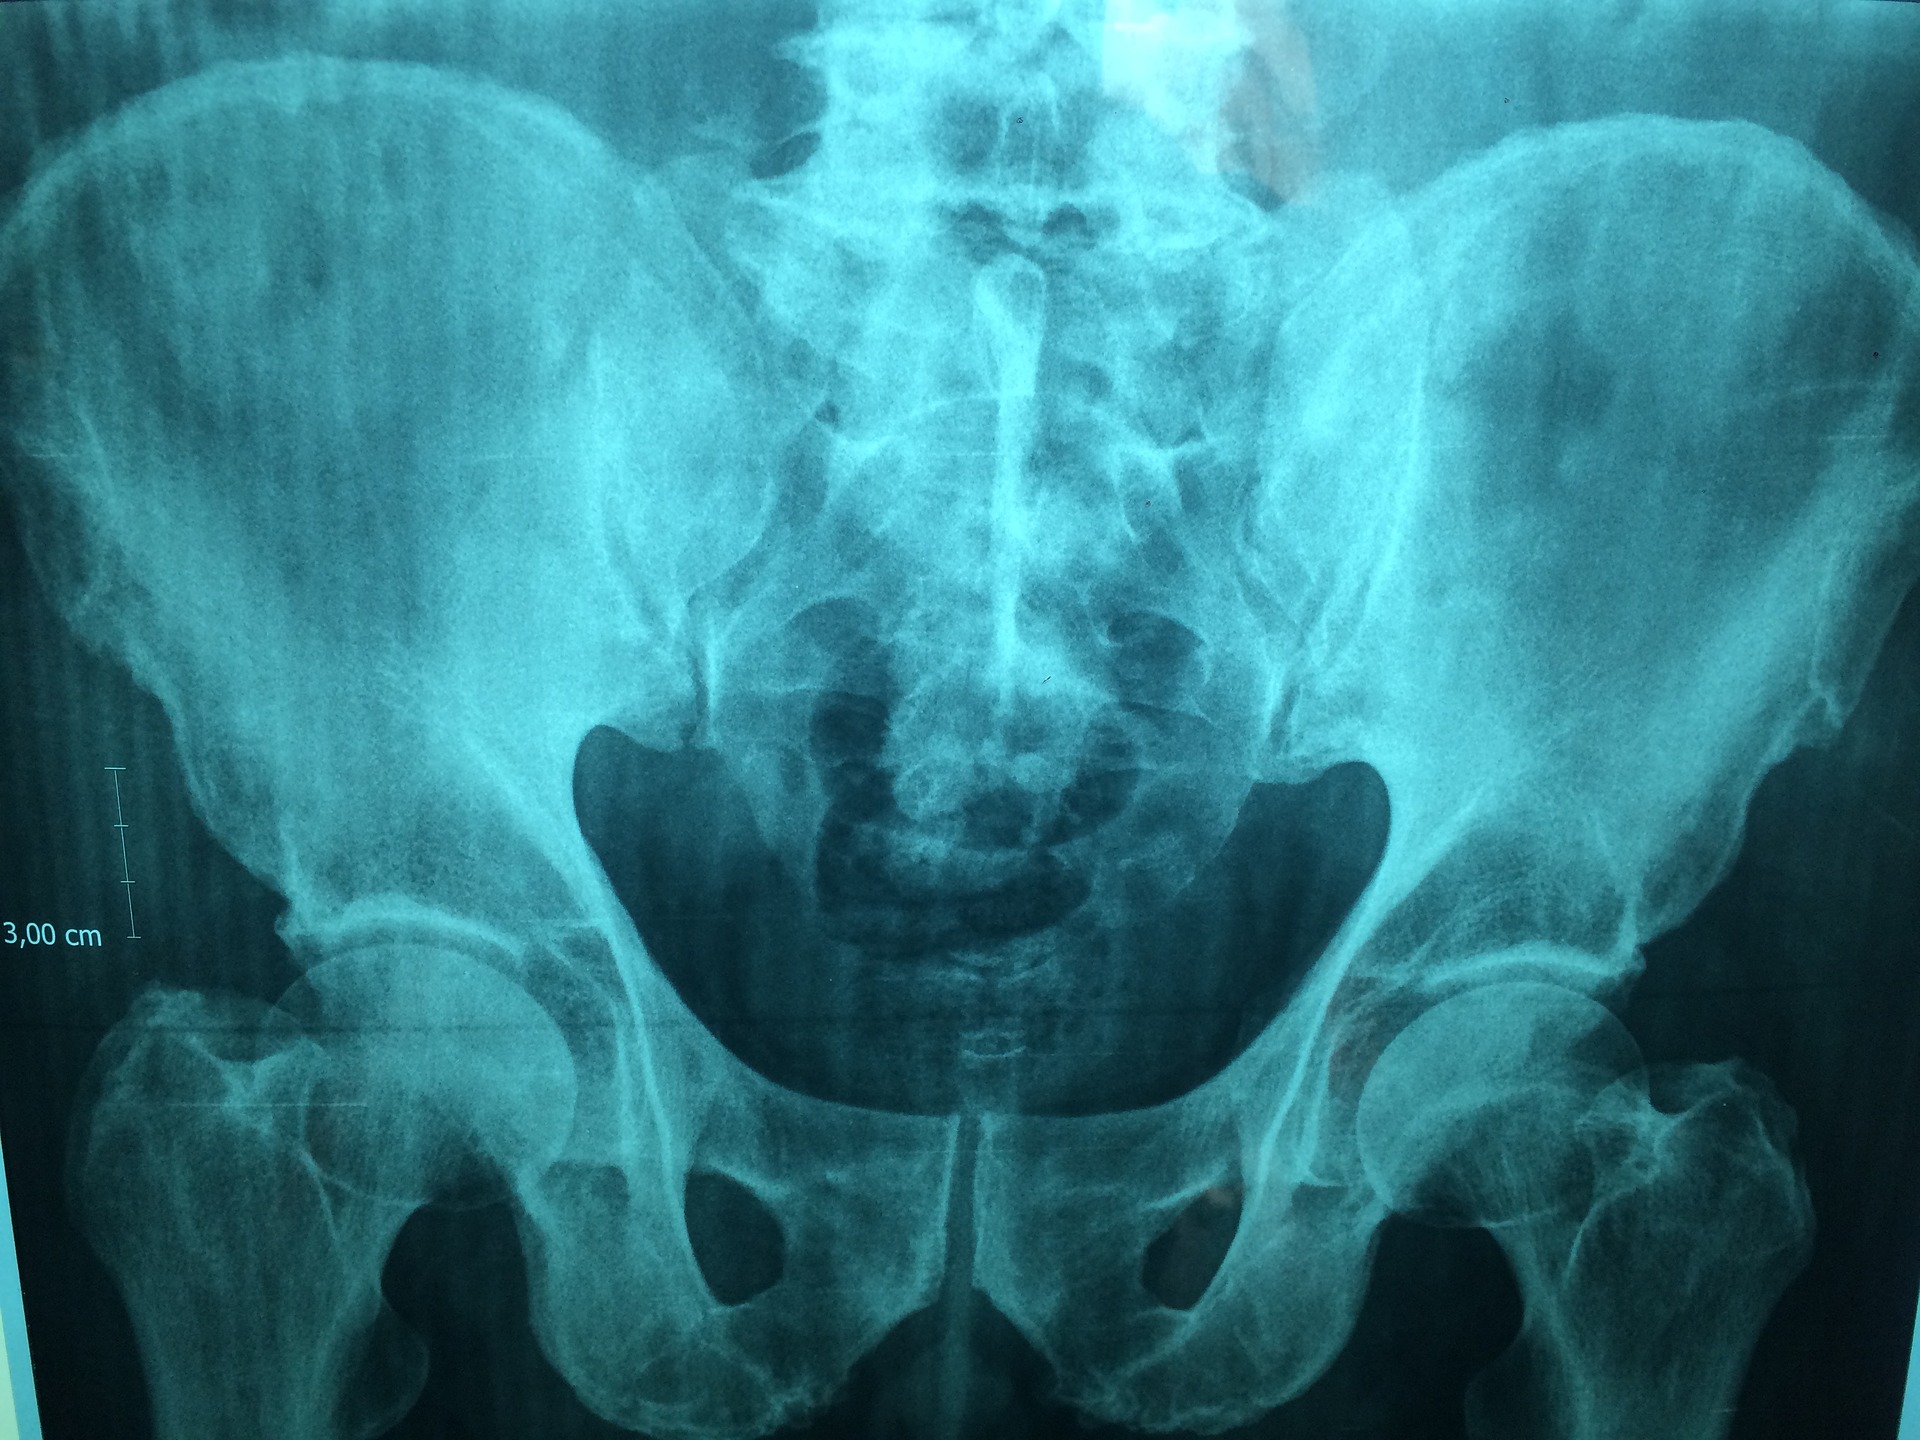

Le fratture pelviche, tipicamente conseguenti a traumi ad alta energia, rappresentano fino al 6,9% di tutte le fratture traumatiche e sono frequentemente associate a lesioni concomitanti. Oltre alle complicanze emorragiche e viscerali acute, queste lesioni espongono i pazienti a un rischio significativo di tromboembolismo venoso (TEV), comprendente trombosi venosa profonda ed embolia polmonare, con incidenze riportate in letteratura estremamente variabili.

Uno studio condotto presso un centro traumatologico di livello I a Riad, in Arabia Saudita, ha analizzato questo problema in una popolazione di pazienti con fratture pelviche e/o acetabolari traumatiche, con l’obiettivo di descrivere l’incidenza della TEV, le strategie di tromboprofilassi adottate e gli esiti clinici associati.